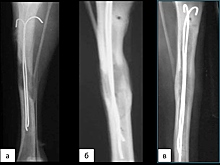

Найден способ ускорить заживление переломов у пациентов с остеопорозом

Томские ученые сумели удвоить скорость заживления переломов

В России научились лечить переломы в два раза быстрее

Имплантаты для аппарата Илизарова в два раза сократили срок удлинения костей